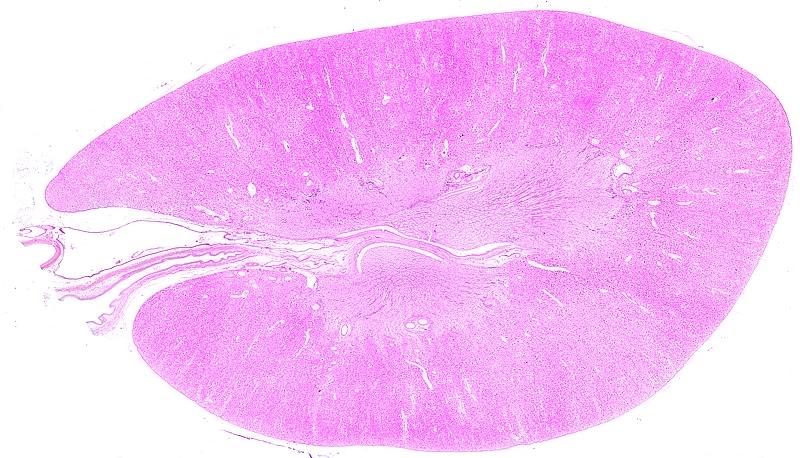

Speiseröhre, Schwein

- 11 Einzelbilder

- 1x Plan

- Autostitch + Photoshop

Infos

- Hier ganz interessant: Das Epithel (begrenzt das Lumen in der Mitte, da rutscht der Speisebrei durch) ist beim Schwein verhornt, bei uns nicht. Man kann sich denken warum, Schweine essen ja fast alles. Deswegen muss es beim Schwein sehr widerstandsfähig sein.

- Die vielen keinen Lappen mit den Punkten zwischen innerem Epithel und äußerer dicker (roter) Muskelschicht sind Schleimdrüsen. Oben links ist ein Ausführungsgang davon zu sehen, er wird auf das Epithel geleitet

- Die Muskulatur außen sorgt für den Transport des Speisebreis